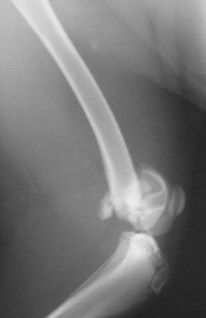

Υπερκονδύλιο κάταγμα μηριαίου σε σκύλο από Πέτρος Μπεάκος14/09/201307/12/2017Σχολιάστε Προεγχειρητική ακτινογραφία. Μετεγχειρητική ακτινογραφία:οστεοσύνθεση με διπλή ήλωση(ενδομυελικώς και χιαστί). Κοινοποιήστε: Στείλε ένα σύνδεσμο σε έναν φίλο(Ανοίγει σε νέο παράθυρο) Email Εκτύπωση(Ανοίγει σε νέο παράθυρο) Εκτύπωση Mοιραστείτε στο Facebook(Ανοίγει σε νέο παράθυρο) Facebook Μοιραστείτε στο X(Ανοίγει σε νέο παράθυρο) Χ Μου αρέσει! Φόρτωση... Σχετικά